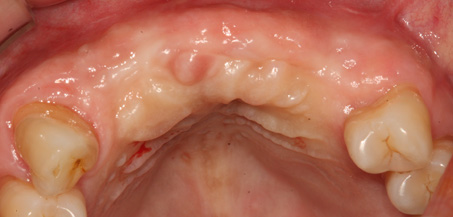

치조골 이식술이란?

치주염 등으로 치조골(잇몸뼈)의 양이 부족한 경우

치조골 이식술을 통하여 충분한 뼈의 양을 확보한 후

임플란트를 식립합니다.

뼈의 밀도가 치밀하고 단단하며, 양이 충분할수록 임플란트의 성공률이 높아집니다.

청담네오플란트는 풍부한 경험의 의료진이 치조골 이식술을 통해 치조골을 적절한 양과

밀도로 재생시킨 후 임플란트를 식립합니다. 뼈의 흡수가 심하지 않아 적은 양의

치조골 이식을 하는 경우 임플란트 식립을 동시에 진행할 수 있지만, 뼈의 흡수가

심하여 많은 양의 치조골 이식이 필요한 경우 치조골 이식술을 먼저 진행한 후,

치조골이 재생되면 임플란트를 식립하여 보다 정밀하고 안전한 시술 결과를 얻을 수 있습니다.

치조골 이식술 전후사진